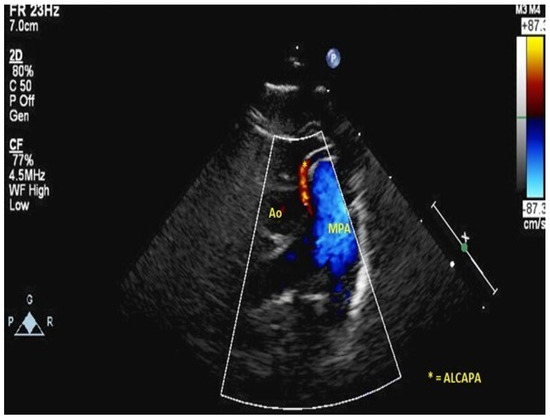

- Frommelt, M.A.; Miller, W.; Williamson, J.; Bergstrom, S. Detection of septal coronary collaterals by color flow Doppler imaging is a marker for anomalous origin of a coronary artery from the pulmonary artery. J. Am. Soc. Echocardiogr. 2002, 15, 259–263. [Google Scholar] [CrossRef]